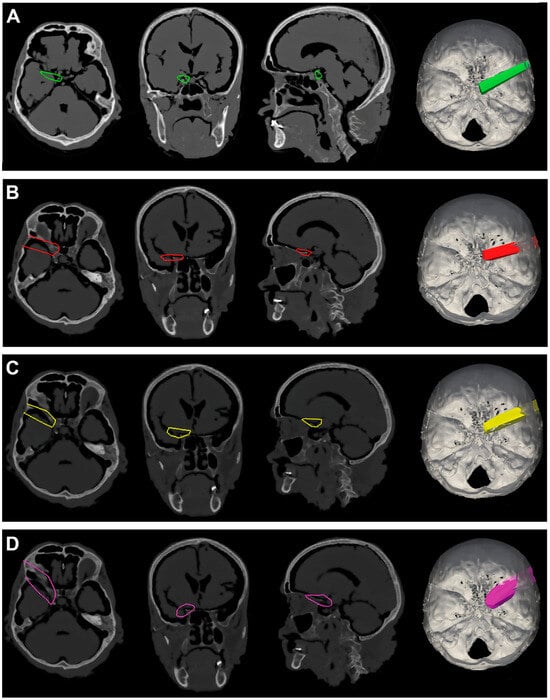

Figure 5.

(A). Exemplificative screenshot from Approach Viewer of the STA with 10 mm of retraction. (B). Exemplificative screenshot from Approach Viewer of the STA with 15 mm of retraction. (C). Exemplificative screenshot from Approach Viewer of the KWA with 10 mm of retraction. (D). Exemplificative screenshot from Approach Viewer of the KWA with 15 mm of retraction.